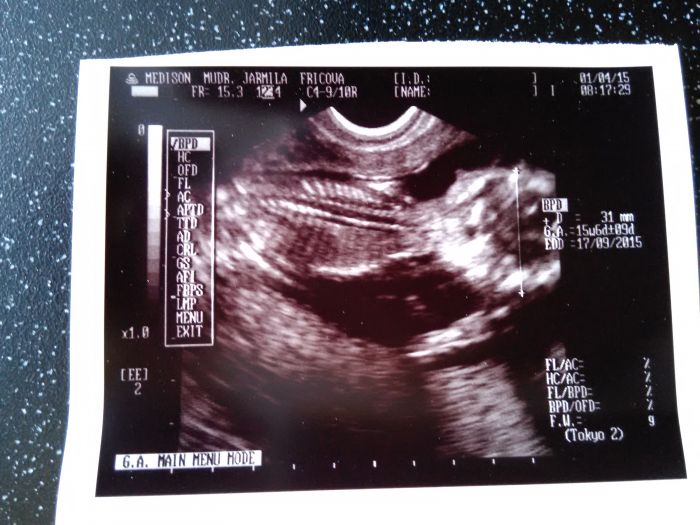

Jinak kontrola dopadla dobře dokonce mi dělala UTZ, prý ho dělá pokaždé mám i foto

dáváte ten UTZ, tak já tu mám jeden z 11+6 tak se taky pochlubím :)